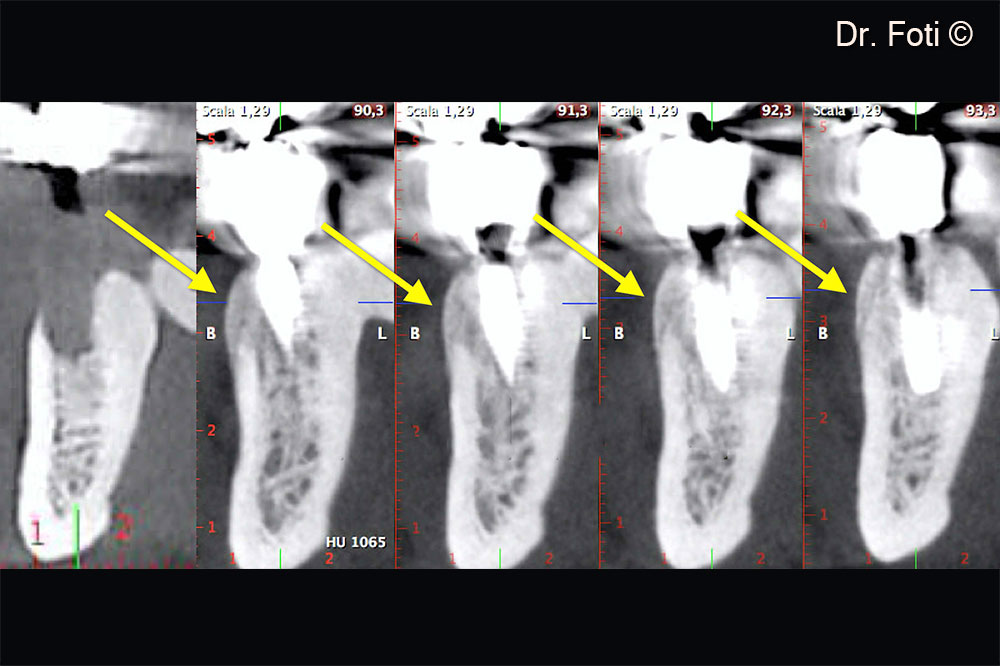

The CBCT scan revealed a vertical defect in position 34

CBCT cross sections at 2 years show the presence of a convex-shaped porcine cortical lamina (arrows). Long-term resorption of the cortical lamina promotes this type of result.